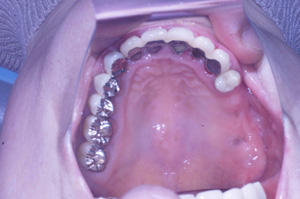

@S.Y‚³‚ñ@ 65Π @’j«@Ž©‰c@@Žèp“ú@‚Q‚O‚O‚W”N@‚UŒŽ‚P‚V“úi‰Îj  ㉺Š{ƒm[ƒxƒ‹ƒKƒCƒhŽg—p@Ö¬“à’ÁÖ@•¹—p

@@@ ㉺Š{  All on ‚U@‘¦Žž‰×d

@    @Rpl Tapered Rp ‚P‚O mm(‚V–{)  @ Rpl Tapered Rp  ‚P‚R mm(‚T–{)@